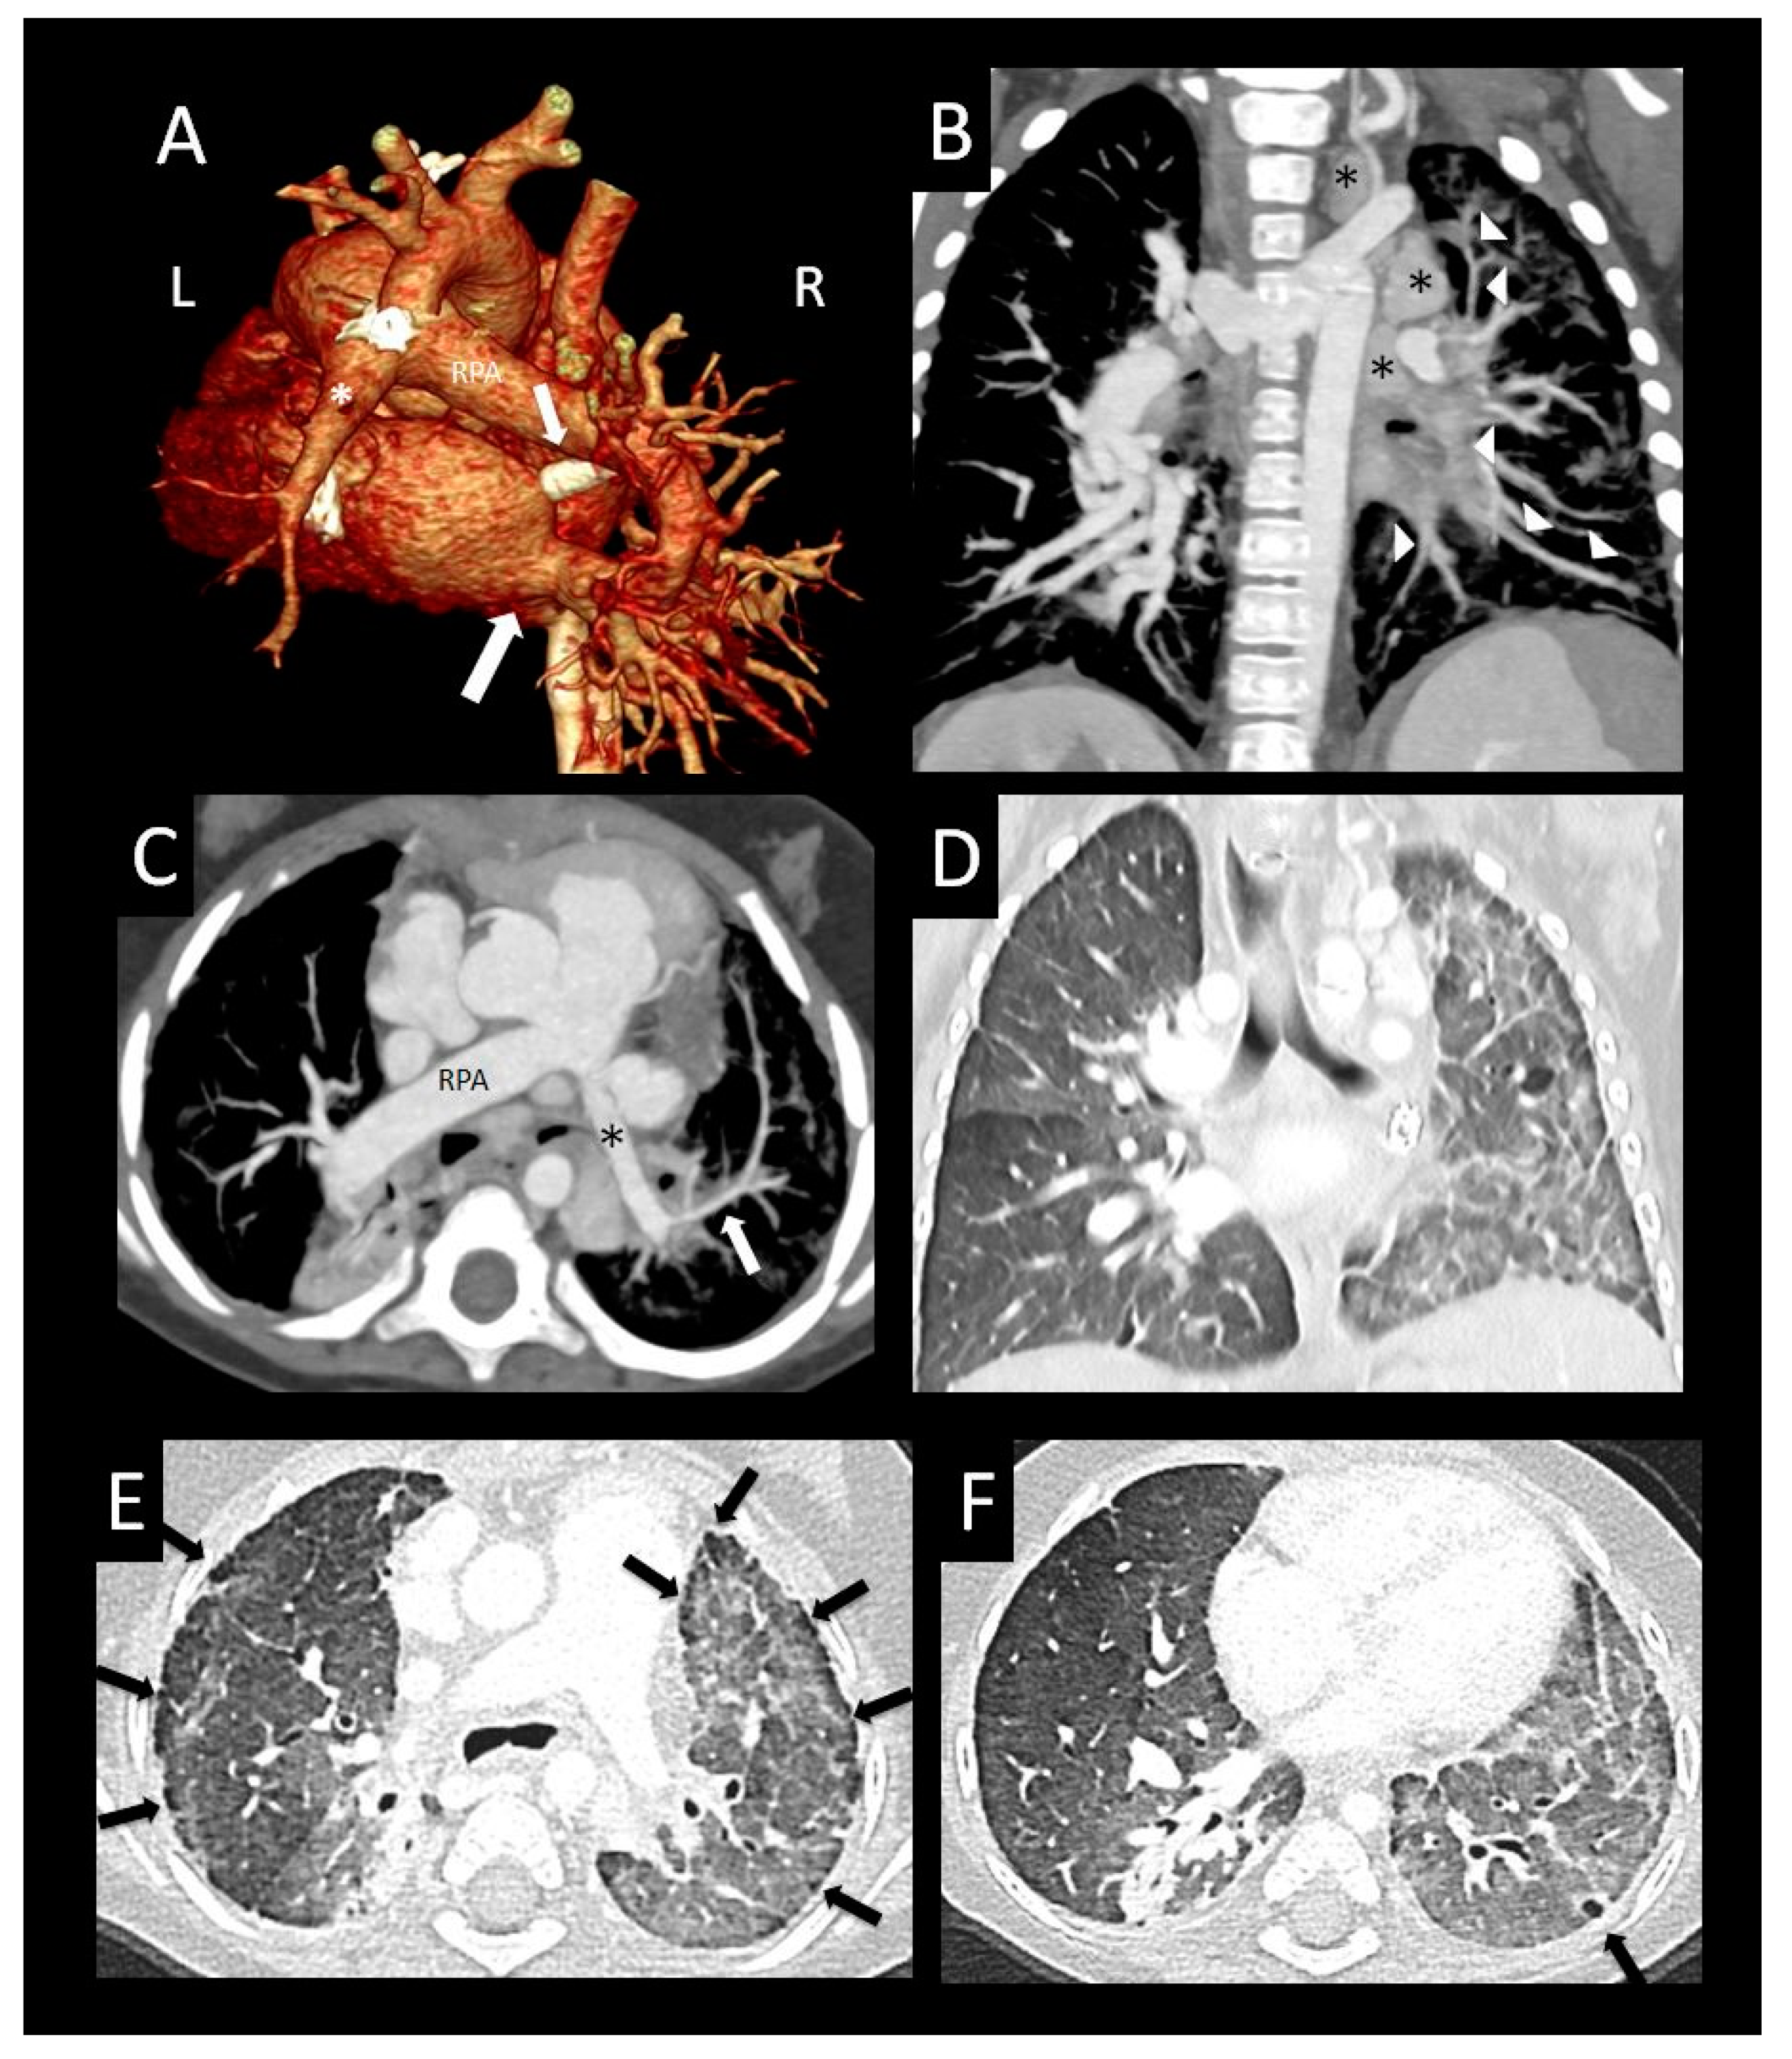

Figure 4. Primary pulmonary vein stenosis. Primary pulmonary vein stenosis diagnosed at 1 year with respiratory distress that was thought to be pneumonia, but failed to improve with antibiotics. Posterior volume rendered CT images show bilateral pulmonary vein stenosis with narrowing of multiple pulmonary veins (arrows), left > right (A), dilated right pulmonary artery (RPA), and small distal left pulmonary artery (*) with hypoplastic left hilar branches (B). Oblique coronal image (C) shows oblique course and decreased enhancement of the left lower pulmonary vein (arrow). Coronal (D) and sagittal (E) images show severe focal narrowing of the left upper pulmonary vein (arrow) as it courses between the left atrial appendage (LAA), a dilated main/left pulmonary artery confluence (*) and left bronchus (arrowhead). The right upper pulmonary vein also has severe focal narrowing as it courses by the dilated right pulmonary artery (RPA) (*) ((F) sagittal oblique image). Coronal lung image (G) shows right > left pulmonary edema, a small right pleural effusion, and left lung hypoplasia. Perfusion scintigraphy anterior image (H) shows 34% left and 66% right lung perfusion with decreased relative perfusion of the left lower lobe.

5. Pulmonary Vein Characteristics

Similar to prior work, we found that many of the stenotic pulmonary veins were compressed by extracardiac structures such as the descending aorta, left mainstem bronchus, or dilated pulmonary artery (Figure 4 and Figure 5); some also had an oblique insertion into the atrium (Figure 6A,B) [16]. We also found that the right lower pulmonary vein tended to be less severely affected and relatively spared of PVS in our study (Figure 5), similar to that seen in prior studies [14,17]. This observation may be attributed to a lower risk of extracardiac compression of the right lower pulmonary vein. In contrast, the left upper pulmonary vein was more commonly stenotic in our study and others. Whereas the normal anatomic relationships of the left superior pulmonary hilum result in a crowded pathway of the left upper pulmonary vein as it courses to the left atrium, passing the left mainstem bronchus and distal main pulmonary artery, the right lower pulmonary vein courses by relatively few structures in normal circumstances. Theoretically, if any of the adjacent structures becomes enlarged (left atrial appendage or main pulmonary artery) or displaced (left main stem bronchus), mass effect with compression leading to stenosis may result. Dilated main and central branch pulmonary arteries associated with baseline pulmonary hypertension may cause a cyclical phenomenon, leading to worsening of pulmonary vein compression and thus worsening pulmonary hypertension. In some cases, an oblique entry of the pulmonary veins into the left atrium resulted in focal stenosis (Figure 6).

PVS, especially when severe, results in redistribution of pulmonary arterial flow away from the affected lung segment [13]. By CT, we observed differential pulmonary venous contrast enhancement in some patients (increased or decreased enhancement; Figure 4, Figure 5 and Figure 7). This variable pulmonary venous enhancement pattern may be attributed to slow flow in the setting of ostial stenosis (increased enhancement), or from decreased perfusion in severely hypoplastic or atretic veins with flow redistribution away from the lung segment (decreased enhancement). Decreased enhancement may result in difficulty identifying veins on CT, especially with volume-rendered reconstructions (Figure 9A,B). The enhancement of the pulmonary veins is not only dependent on the relative flow distribution to each lung segment, but also depends on the timing of the contrast bolus when the scan is acquired. In addition, there may be preferential enhancement of left- or right-sided pulmonary veins when intravenous contrast is injected into patients with bidirectional Glenn (Figure 10) or Fontan circulations. Therefore, knowledge of the sources of pulmonary artery blood flow and the site of contrast injection should be taken into consideration before attributing variation in pulmonary vein enhancement to PVS. Correlation with radionuclide perfusion lung scans or obtaining iodine maps with dual-energy CT acquisitions at the time of the CTA may help to identify segments with decreased perfusion (Figure 4 and Figure 10) [18]. Timing of the scan acquisition during the intravenous contrast injection can be challenging, especially when patients are tachycardiac and transit times through the circulation are hyperdynamic, particularly in infants. Because of this phenomenon, we suggest a delayed acquisition of at least 25–30 s from the start of contrast injection, to ensure that there is some enhancement of peripherally hypoplastic or atretic veins.